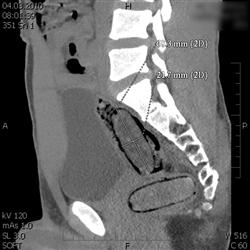

Olomoučtí celníci prováděli ve čtvrtek 4. března v nočních hodinách kontrolu mezinárodního rychlíku. Ten jel z Polska do Rakouska. Všimli si jednoho z cestujících, který vykazoval indicie naznačující pašování drogy. Pocházel z oblasti západní Afriky a trvalý pobyt měl v Evropské unii. Celníci provedli další kontroly za účelem detekce přítomnosti omamné psychotropní látky. Ty potvrdily výskyt drogy v těle. Následné CT vyšetření s jistotou prokázalo, že muž ukrývá v tělních dutinách čtyři kontejnery s neznámou látkou. Po vyloučení těchto předmětů z těla, za přítomnosti celníků, byl proveden drogový test a orientační vážení. Pasažér převážel v tělních dutinách 114 gramů kokainu. V lednu byl odhalen podobný případ, kdy cizinec přepravoval stejným způsobem 160 gramů kokainu.